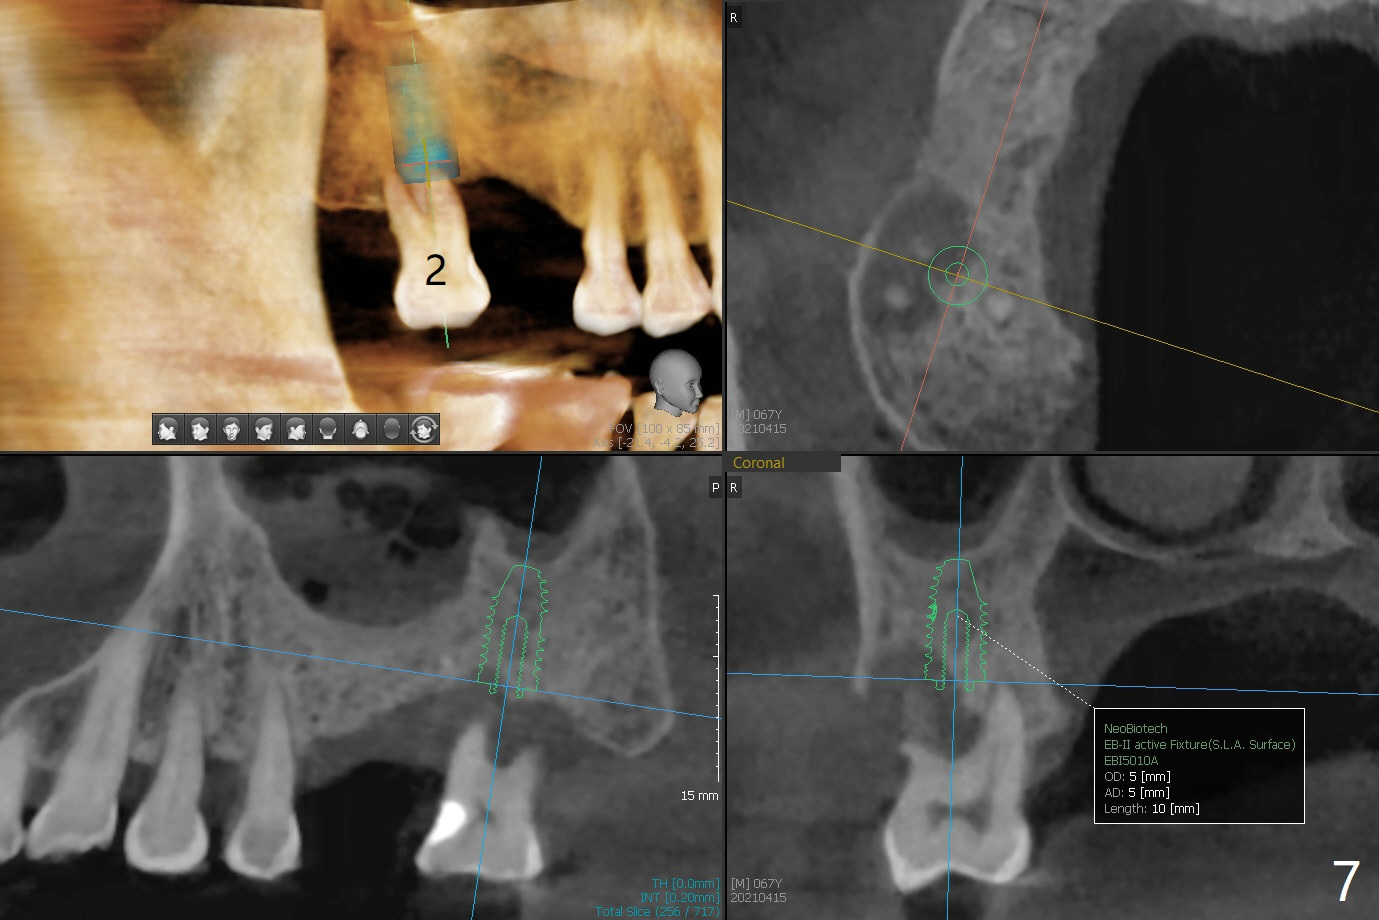

当3号牙短小植体植入后(图一(骨质密度高)),病人纳闷为什么不给他装临时牙冠,术后两个月又打电话要求提前修复,因为放置愈合基台,他无法使用局部托牙(单个牙),而14号牙即刻植牙即刻修复。他无法理解我们苦衷,有什么补救方法?

使用来自钻头的自体骨做提升,植体植入后,颊侧骨板薄,刚好骨下。使用5.5毫米profile drill后,放置愈合基台,术后三个月脱落,他再次要求修复,甚至提出退款,不愿意回诊所,因为他有糖尿病,新冠病毒高危人群。 放置小号愈合基台(图二)。他原来托牙是Valplast,没有occlusal rests,不能经过修改临时使用,可能将直接放置修复基台做临时牙冠。放置修复基台后(图三(术后三个月)),制作临时牙冠时,发现前者有些松动,后者就没有粘固。当基台完全就位,它最冠方与植体没有间隙(箭头),根方有间隙(空心箭头)。其实愈合基台也是一样(图一,二)。后来植体松动(术后4个月),拔除,植骨(图四),颊侧骨板缺失(图五:B)。植骨后5个月2号牙疼痛需要拔除种植(图七),与3号牙一起种植(图六),颊侧骨板修复,但是高度有所下降(箭头)。The narrow ridge with the intact buccal plate (Fig.8 >) can hold a 4x8.5 mm implant. The buccal plate is lost 4 months postop (Fig.9) and restores 5 months post graft (Fig.10). Return to Upper Molar Immediate Implant, No Deviation Coronal and Apical Gap in IBS implant Protect Graft Xin Wei, DDS, PhD, MS 1st edition 06/22/2020, last revision 05/02/2021